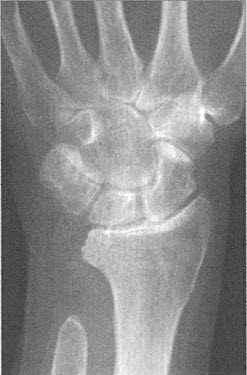

Eine Verdachtsdiagnose kann bereits durch die Patientenbefragung und das aktuelle Beschwerdebild gestellt werden. Gesichert wird die Diagnose einer Arthrose dann durch ein Röntgenbild. Findet sich nur eine leichte Arthrose, müssen möglicherweise Zusatzuntersuchungen durchgeführt werden. Bei fortgeschrittenen Arthrosen mit Gelenkzerstörung findet sich im Röntgenbild nur noch ein schmaler oder auch gänzlich fehlender Gelenkspalt (Abb. 1a bis 1c).

Teilversteifungen

Nicht verheilte Bandverletzungen zwischen den einzelnen Handwurzelknochen und nicht verheilte Knochenbrüche können chronische Instabilitäten zur Folge haben. Diese führen im Spätverlauf dazu, dass die Gelenkflächen zerstört werden. In einigen Fällen ist es möglich, lediglich die betroffenen Handgelenkabschnitte zu versteifen und so eine Restbeweglichkeit zu erhalten.